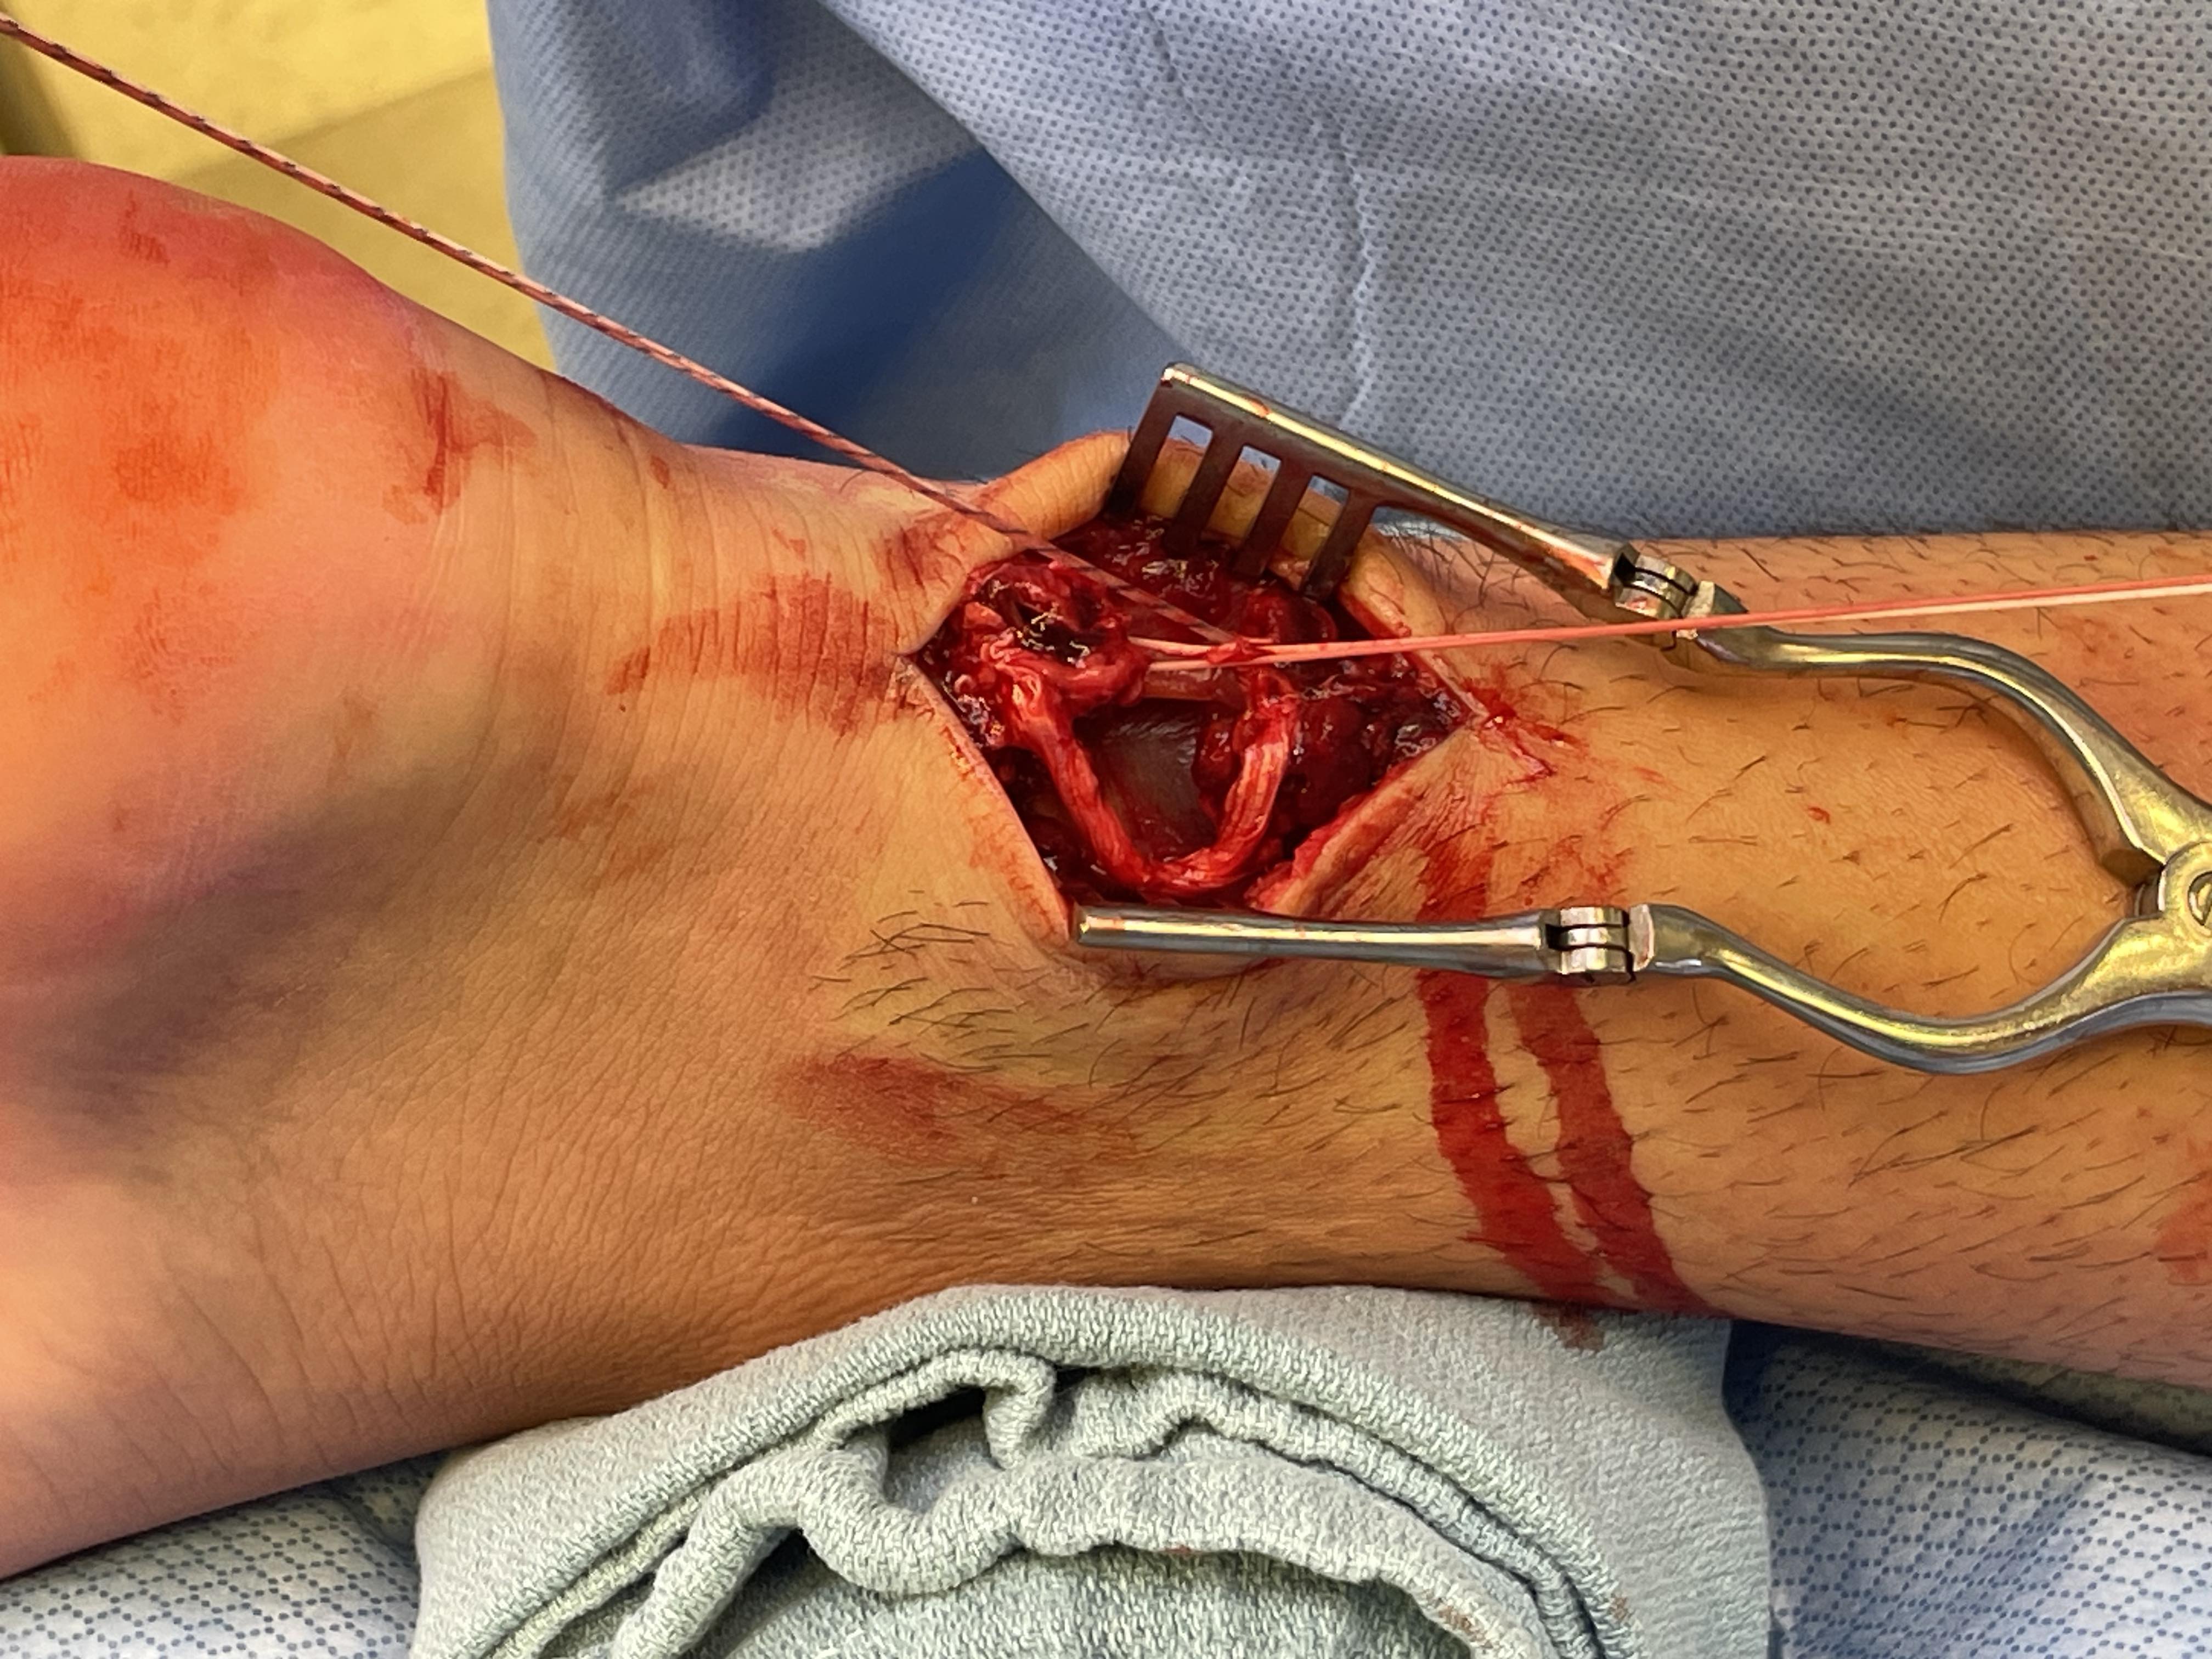

Open tendoachilles repair

Technique

Vumedi open achilles tendon repair

Prone position with tourniquet

- slightly medial incision to protect sural nerve

- full thickness skin flaps to paratenon

- identify and protect sural nerve

- divide paratenon longitudinally

- can incise paratenon in the midline anteriorly which increases tissue available for closure

- Bunnell Suture / Krackow suture x 2 with high strength suture / fibre wire

- one in proximal and one in distal tendon ends

- tie via two knots with foot fully plantar flexed

- +/- augment with circumferential 4.0 suture to minimize bunching

- careful closure of paratenon to prevent skin adhesions

- front slab in plantarflexion 2 weeks

- then standard accelerated rehabilitation

Anterior release of paratenon to allow posterior closure over achilles repair

Repair with proximal and distal Krackow high strength sutures